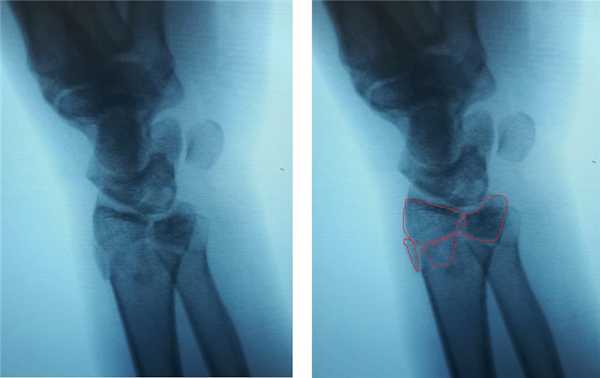

Клинический пример. Пациентка С. 36 лет, травма при падении во время матча по большому тенису, получила закрытый оскольчатый перелом дистального метаэпифиза лучевой кости с большим количеством мелких фрагментов в метафизарной зоне.

На 7 сутки после получения травмы пациентка обратилась в Клинику К+31, учитывая нестабильный характер перелома предложено оперативное вмешательство. Для остеосинтеза использована пластина VA-LCP™ Volar Rim Distal Radius Plate.

Такая фиксация даже при таких тяжёлых дистальных переломах позволяет начать раннюю активизацию, занятия лечебной физкультурой в кратчайшие сроки после операции. Для профилактики КРБС при тяжёлых оскольчатых переломах рекомендуется использование витамина С в дозе 200 мг в сутки до 45 дней после травмы, возвышенное положение конечности в покое, хивамат, гипербарическая оксигенация, использование таких препаратов как актовегин и трентал.